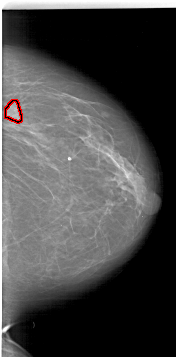

A_1788_1.RIGHT_MLO

RIGHT_MLO LINES 6031 PIXELS_PER_LINE 3286 BITS_PER_PIXEL 12 RESOLUTION 43.5 OVERLAY

FILE: A_1788_1.RIGHT_MLO.OVERLAY

TOTAL_ABNORMALITIES 1

ABNORMALITY 1

LESION_TYPE MASS SHAPE LOBULATED MARGINS ILL_DEFINED

ASSESSMENT 4

SUBTLETY 4

PATHOLOGY BENIGN

TOTAL_OUTLINES 1

BOUNDARY